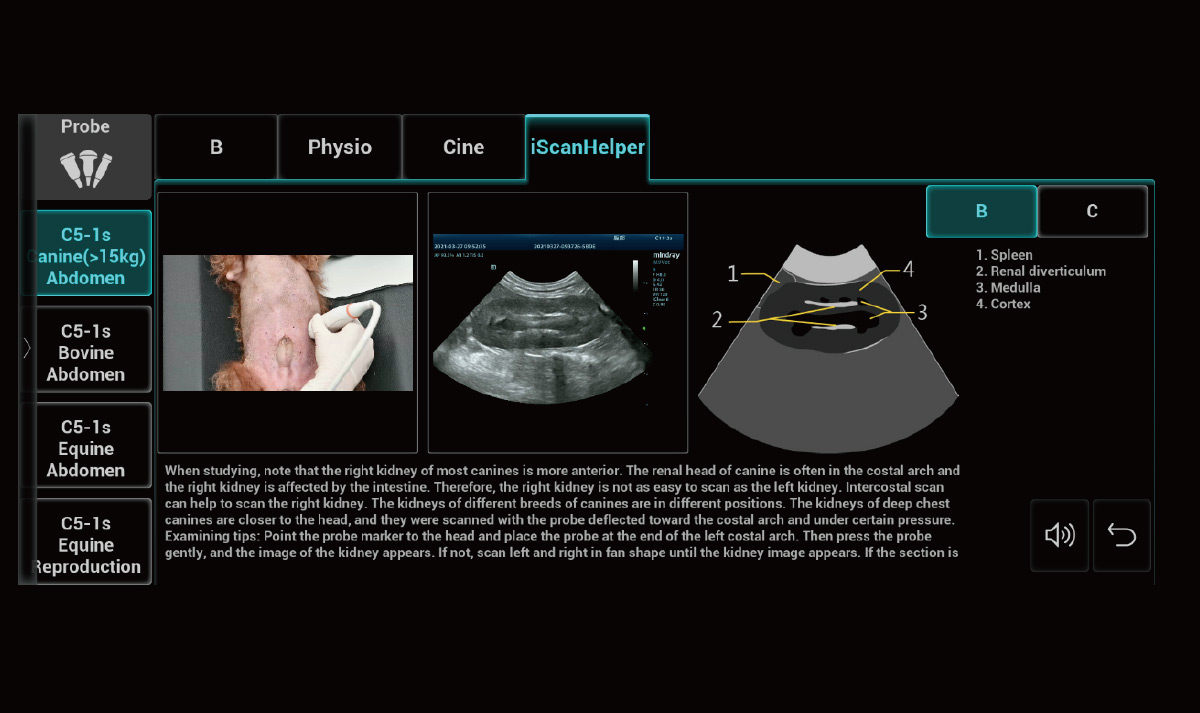

2iScanhelper

Experto a su alrededor, proporciona imágenes de referencia de escaneo y guía de demostración